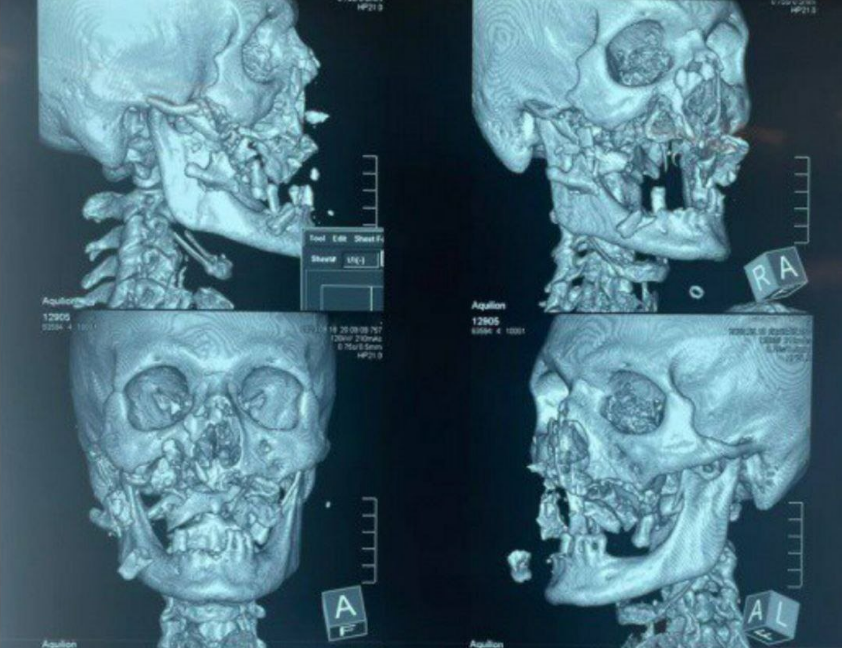

Врачи больницы в столице Хакасии Абакане буквально по частям смогли собрать лицо 42-летнего мужчины, на которого напал медведь.

"В ходе встречи с медведем серьезно пострадали кости лицевого скелета: были полностью раздроблены скуловые и кости носа, верхняя челюсть с зубами и нёбом", - приводит Минздрав.

Фото: Минздрав Республики Хакасия